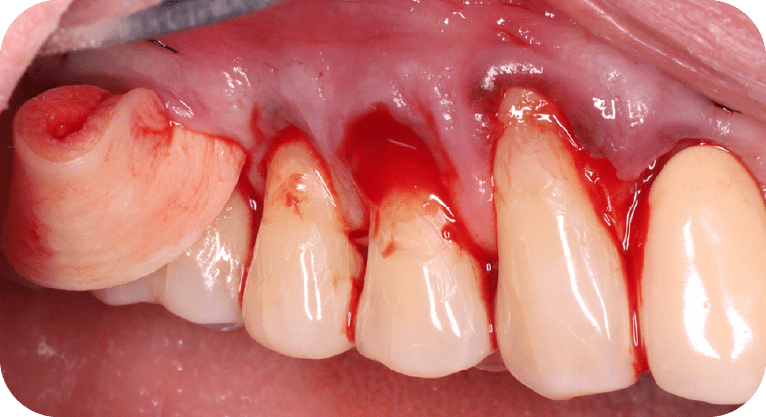

Paciente masculino, “65” años

Tratamiento: Cirugía de encías

El paciente presentaba sensibilidad dental causada por la exposición de los cuellos dentales, por lo que se realizó una cirugía de recubrimiento radicular con injerto gingival y reposicionamiento de encía, logrando

proteger las raíces expuestas, reducir la hipersensibilidad y mejorar tanto la función como la estética periodontal, con resultados satisfactorios para el paciente.